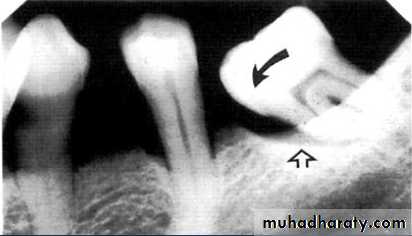

2.Vertical bone loss:- when there is greater bone loss in one tooth than on the adjacent tooth, so the bone level is not parallel with a line joining the CEJ.

Detection of Periodontal Disease

Vertical osseous defects can be divided into two primary types: Interproximal crater is a two-walled, trough like depression

that forms in the crest of the interdental bone between adjacent teeth.

The Infrabony defect is a vertical deformity within bone that extends apically along the root from the alveolar crest.

3.Furcation involvements:

Bone loss in the furcation area of the roots which is evidence of advanced disease in multirooted

teeth.

Initially seen as widening of the PL space at the crest of

the furcation . As lesion progresses, the bone

loss progresses apically.